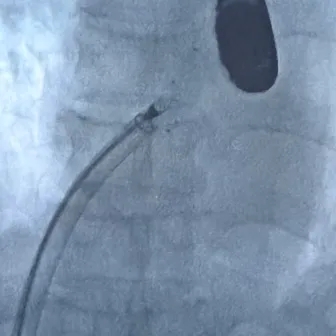

展开左盘面

推出左盘3个Mark及腰部Mark,牵拉成型线使左盘面成型

后撤钢缆和鞘管,使左盘面贴靠房间隔

展开右盘面

后撤鞘管展开右盘面,前推钢缆使右盘面成型

超声下,封堵器左右盘面贴合房间隔两侧

成型锁定

鞘管抵住封堵器后,前顶钢缆固定,牵拉成型线锁定

锁定后,超声下观察封堵器结构,盘面呈标准的三明治结构,成型良好

牵拉试验

轻轻推拉钢缆,超声下封堵器与钢缆整体移动,结构稳定无散开,锁定成功

释放封堵器

撤出成型线后,前抵鞘管,逆时针旋转钢缆,5个Mark相对位置不变,封堵器释放成功